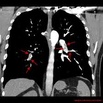

Zator tętnicy płucnej jest główną przyczyną chorobowości I śmiertelności wśród chorych poddawanych zabiegom kardiochirurgicznym w trybie pilnym, z całkowitą śmiertelnością wahającą się od 6% do aż 85%. Choć leczeniem pierwszego rzutu jest postępowanie niechirurgiczne lub interwencja przezskórna, to u chorych we wstrząsie kardiogennym leczenie operacyjne ciągle pozostaje metodą z wyboru. Nasz ośrodek regularnie wykonuje operacje embolektomii tętnicy płucnej, których rezultat jest lepszy, niż podają aktualne doniesienia. W związku z tym przeprowadziliśmy retrospektywną analizę wyników leczenia chorych z zatorem tętnicy płucnej i rodzaju anestetyków stosowanych podczas leczenia.

więcejNiestabilność hemodynamiczna u chorych poddawanych embolektomii tętnicy płucnej: doświadczenia własne